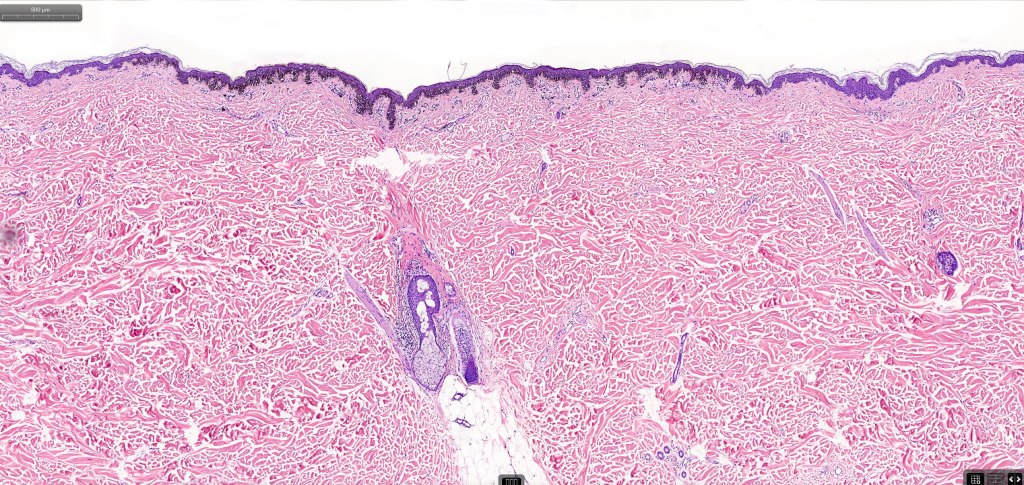

- A broad lentiginous proliferation of atypical melanocytes unasscoiated with any loss of the rete ridges

8. An invasive component may be present